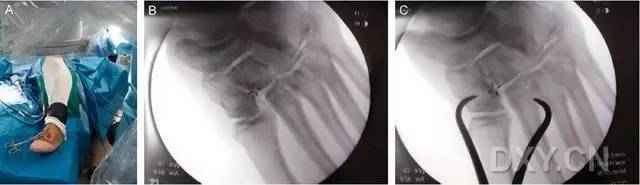

这一损伤的传统固定方式是将 1 枚螺钉(以下简称为 Lisfranc 螺钉)经内侧楔骨向第 2 跖骨基底置入(图 1)。

图 1. 传统的 Lisfranc 螺钉置入方法